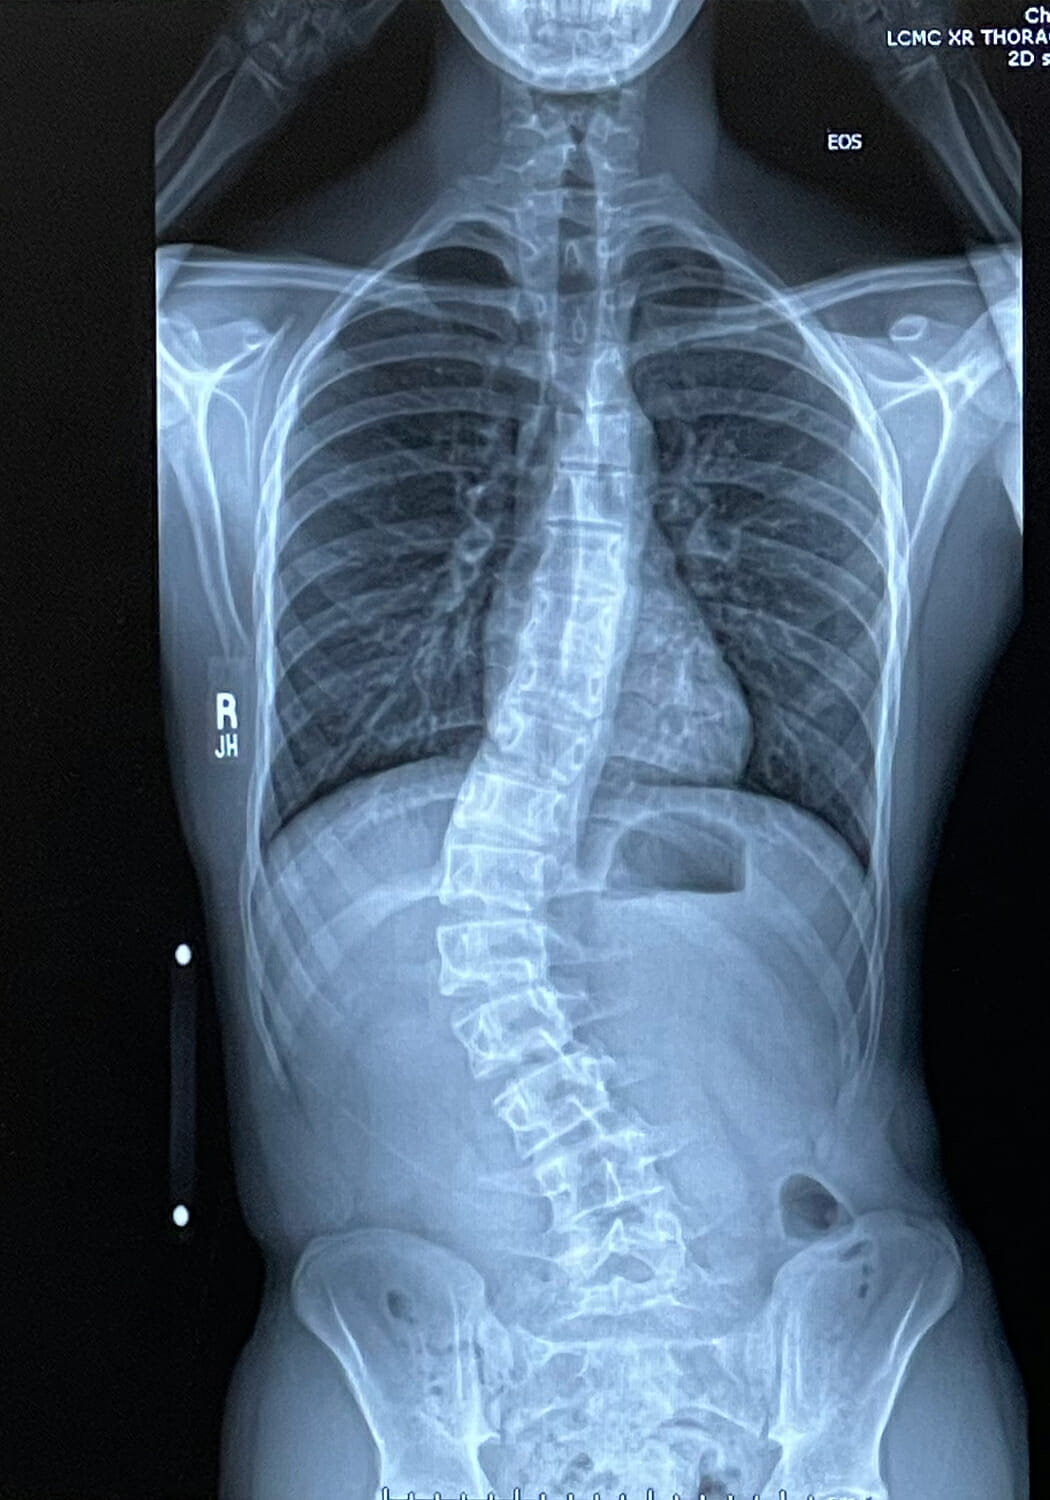

The X-Rays

I picked up his x-rays that afternoon from the hospital and pulled them up on my computer, convinced they had made a mistake (as if I am in any way qualified to determine whether medical professionals have made a mistake or not ????) and my heart sank when I saw them. I felt so guilty for not really listening to him when he said his back hurt, that I hadn’t pushed for more regular checkups, that it was somehow my fault. I thought scoliosis was just a matter of straightening out the spine and, because it’s flexible, that should be relatively easy. I didn’t realize that that is how the bones had grown and straightening them out without surgery is virtually impossible.

In my mind, surgery was the worst possible outcome. I looked into “scoliosis camp” and Schroth physical therapy, but we don’t have any Schroth therapists near us (and it’s so incredibly expensive) and ScolioSmart (scoliosis camp) felt scammy to me. I didn’t realize that braces aren’t designed to correct the curve, they just prevent it from getting worse (I also didn’t realize how terrible bracing is…it’s basically a torso cast that has to be worn nearly constantly for years.) Regardless, he wasn’t a candidate for bracing because the curve was too severe and he was too old and close to being done growing, When I showed the x-rays to a few friends in the medical/orthopedic/physical therapy industry, the consensus was basically that surgery was the only way to correct it and prevent it from getting worse was surgery. I cried a lot. He was anxious and angry. A good time was had by all.

In late October 2020, about 10 days after that first visit with the pediatrician, we went to New Orleans to meet with his surgeon for the first time. They did more x-rays and discovered that the curve was even more severe than the local hospital had said (49-50 degrees instead of 47.) The surgeon said that surgery wasn’t something we were going to rush into, but we needed to keep an eye on things. He talked about all the options with me and explained the pros and cons in a lot of patient detail. He wanted to see if and how the scoliosis was still progressing, so he prescribed physical therapy, vitamin D, calcium, and magnesium supplements, and told us to come back in 4 months.

When we went back in February, the x-rays showed that his curve had progressed from 49-50 to 54-55 degrees (in 4 months!) At that point, the doctor said surgery was definitely the best option and I agreed.

A: By the time he had surgery, 55 degrees. Severe scoliosis starts at 40 degrees.